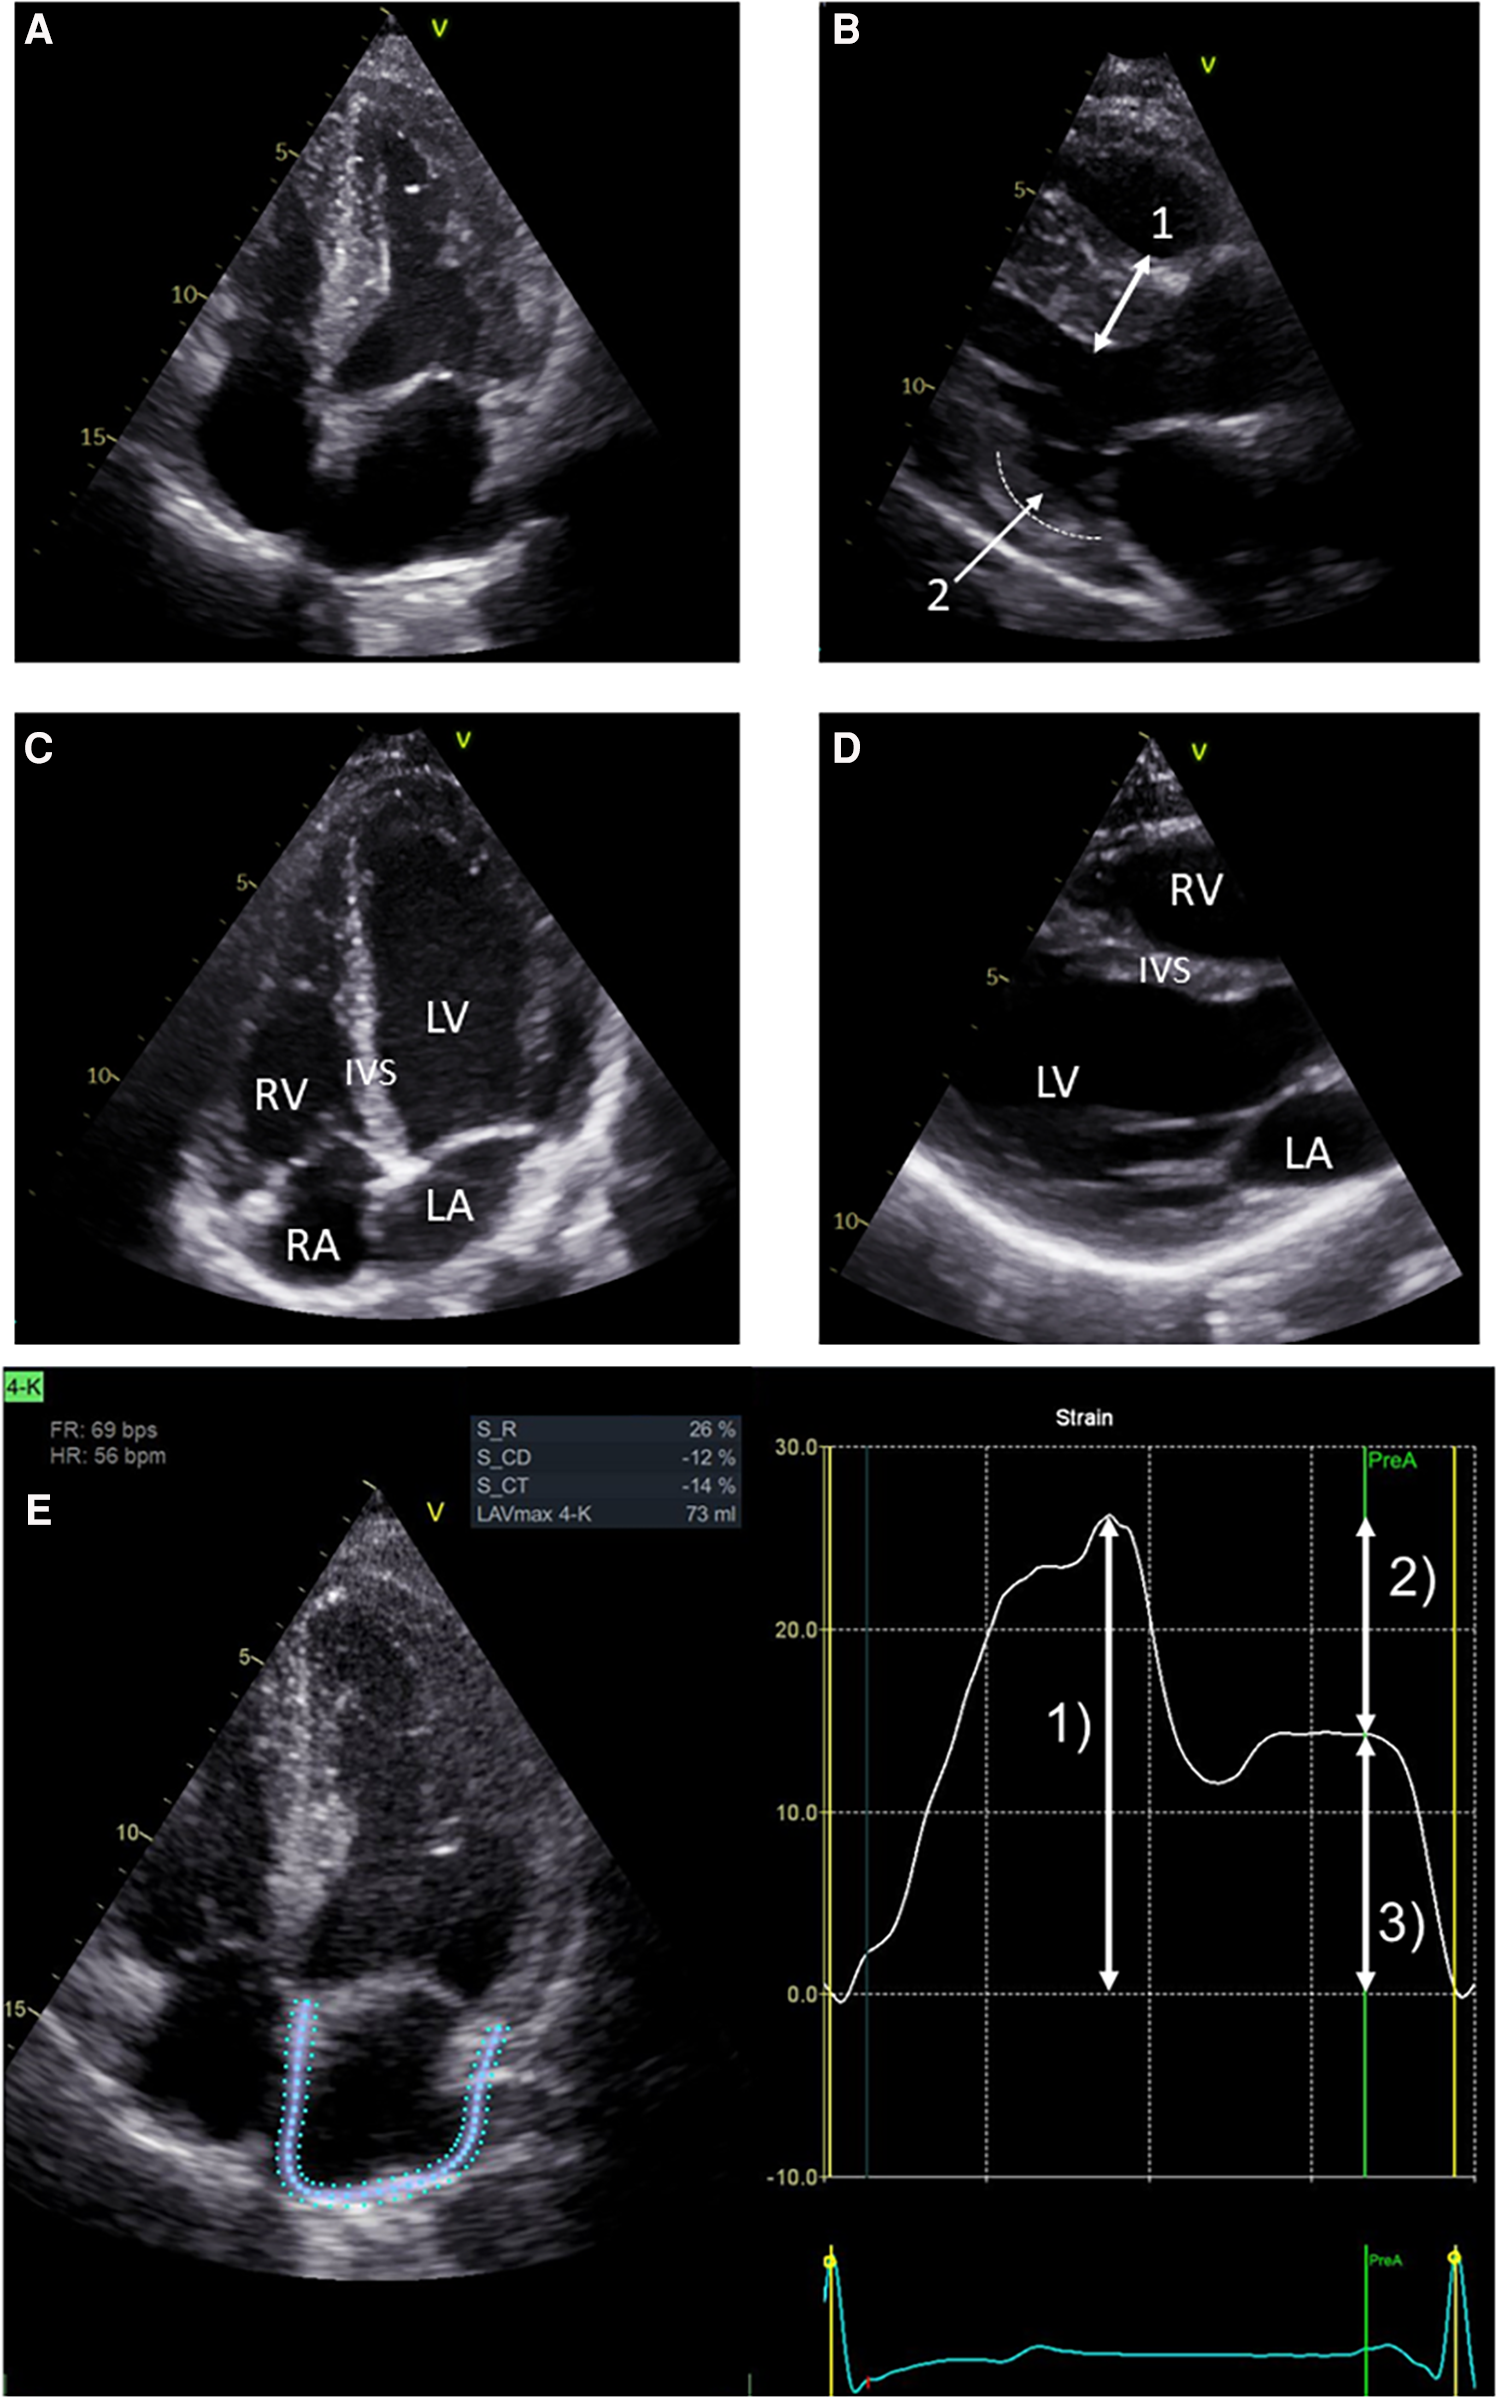

Table 2 presents the baseline cardiac parameters and strain analyses. Supplementary Table S2 presents the differences between males and females. Figure 1 shows representative echocardiographic images of LVH in a male patient with FD cardiomyopathy compared with normal cardiac findings in a female patient from the untreated control group. Figure 1E illustrates an example of LAS and the resulting strain measurements drawn as a curve. Intraventricular septum thickness and LVMi values were in the reference range in untreated females (Figures 2A,B). The mean interventricular septum thickness was increased in ERT- and migalastat-treated males and females. The mean LVMi was within the reference range only in migalastat-treated females (Figures 2A,B). Furthermore, the global longitudinal strain (GLS) average values differed significantly between treated and untreated females (Table 2). A comparison to reference values (18) demonstrated that the mean GLS values for untreated females were within the reference range, whereas those in treated patients (females and males) were not (Figure 2C). LAS consists of three phases of the LA: left atrial reservoir function (LaSr), left atrial conduit function (LaScd), and left atrial contraction “booster” strain (LaSct) (Figure 1E). At baseline, LaSr was reduced in the female ERT group compared with the untreated females. A trend toward reduced LaSr was observed in the female migalastat group at baseline. In addition, LaScd was reduced at baseline in FD-specific treated females in comparison to untreated females. Overall, treated males showed lower values for LAS at baseline compared with females. The LA volume index and strain analyses for RV showed no differences between the groups (Figures 2D,H,I). Independent of sex, further cardiac parameters were comparable between migalastat- and ERT-treated patients.

Figure 1

Representative echocardiographic four-chamber views. (A) Echocardiographic four-chamber view of a 48-year-old male treated with ERT. Note the LVH of the left ventricle (LV). (B) Echocardiographic PLAX view of the same patient. Bidirectional arrow (1) marks septal hypertrophy (measured 15 mm). Arrow (2) marks thinning of the basal infero-lateral wall (dotted line), which is sometimes observed in advanced LVH. (C) Echocardiographic four-chamber view of a 26-year-old female from the untreated control group. Left ventricle (LV), right ventricle (RV), left atrium (LA), and right atrium (RA). (D) Echocardiographic PLAX view of the same female. This view and (C) show an interventricular septum (IVS) of normal size. (E) LA strain in echocardiographic four-chamber view on the left side. Note the blue and dotted defined regions of interest (ROI) overlapping the LA walls. Strain values determined by speckle tracking over time are shown on the right. The trigger used for the LA phases is R-R interval. Arrow (1) represents the reservoir function (LaSr) of the LA. Arrow (2) represents the conduction function (LaScd) of the LA. Arrow (3) represents the contraction function (LaSct) of the LA. In the LA cycle, an increase in strain is observed in systole, representing the expansion of the LA. Peak strain is reached at (1). The mitral valve opens, and in diastole, the LA releases blood into the LV represented by the conduit phase. The conduit phase ends by contraction, indicated by the A wave on the ECG. Contraction of the LA enhances LV filling and is represented by (3), which completes the cycle leading back to (1) (analyses for this image used EchoPAC™, version 204, GE).